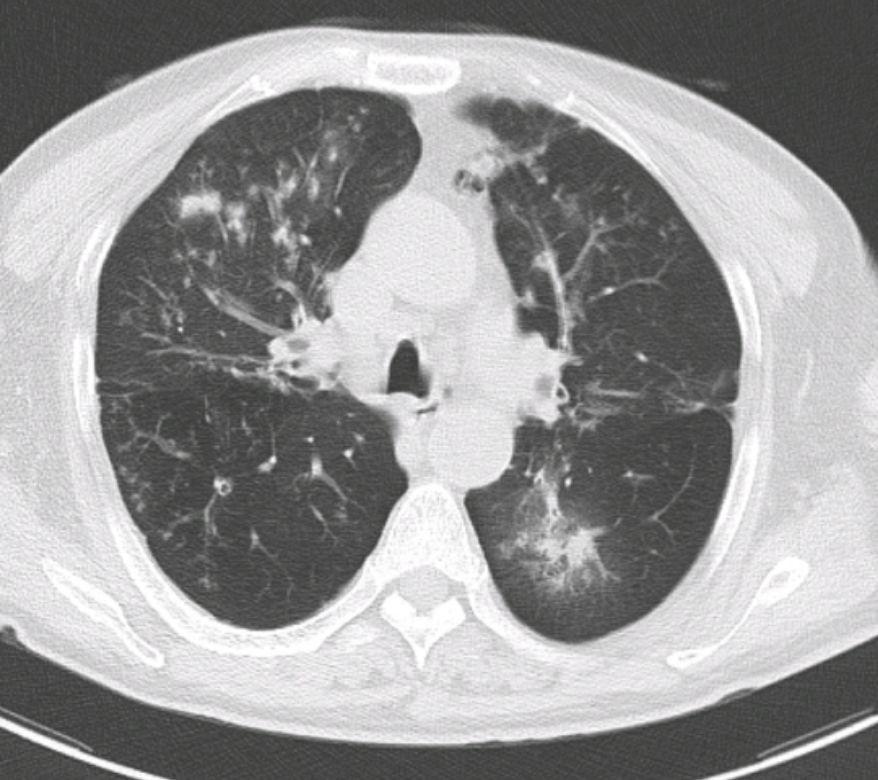

这位男性患者35岁,在体检中发现右肺有一个磨玻璃结节,已经随访快一年了,大小和形